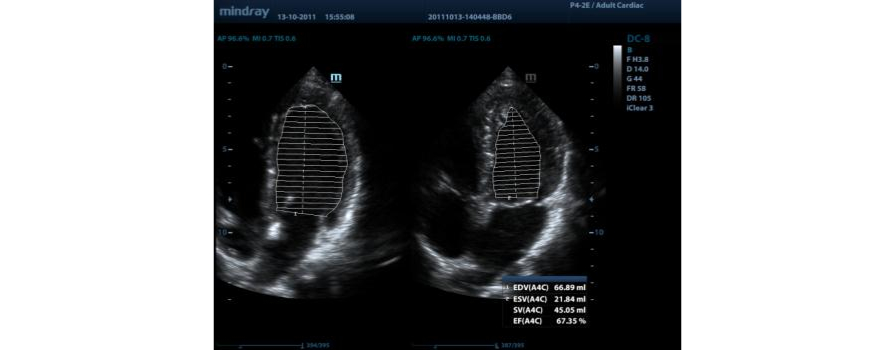

Fracci├│n de eyecci├│n autom├Ītica (AutoEF)

Una forma inteligente de analizar las 2D para reconocer autom├Īticamente los niveles diast├│licos/sist├│licos y generar la estimaci├│n diast├│lica, el volumen diast├│lico, la fracci├│n de eyecci├│n (EDV/ESV/EF), etc. resultantes del m├®todo Simpson.